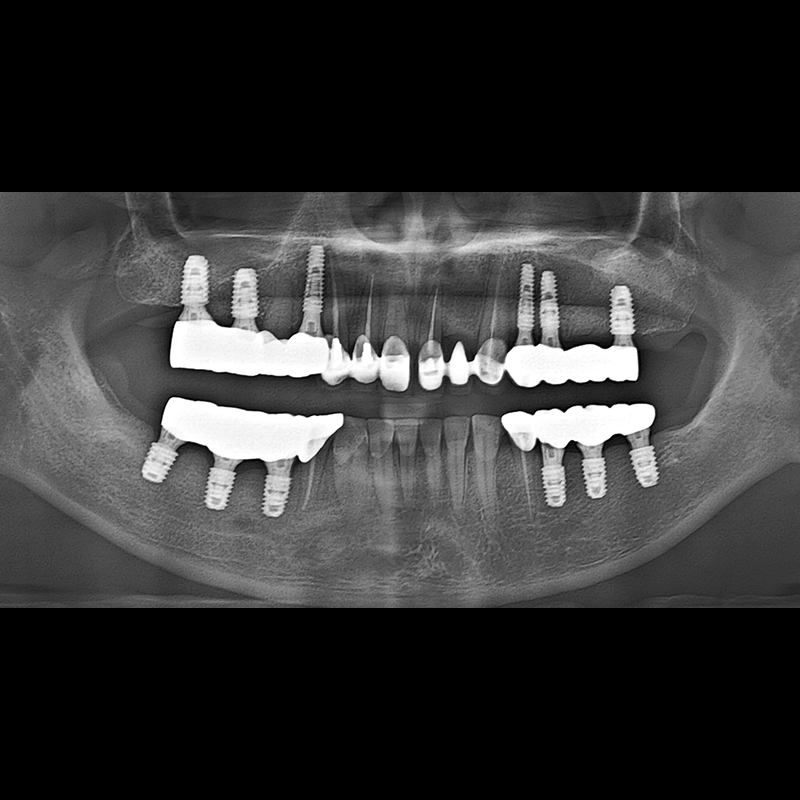

BEFORE AFTER

임플란트 전후사진 2025.05.30

결손된 치아 부분과 살리기 힘든 치아 위치에 임플란트를 식립하였습니다.